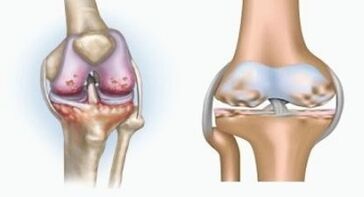

Arthritis

Arthritis is an inflammation of the connective tissue - a synovial membrane that contains many vessels and provides lymph flow.The inflammatory process leads to a violation of articular tissue food, as a result of which the production of articular lubrication - synovial fluid is limited.

Arthrosis is a degenerative-district process associated with the destruction of the knot's cartilage tissue.The jump is gradually destroyed, dry, the distance between the bones of the joint decreases, which is the cause of the pain.In severe forms, destruction affects the bones.They become more porous, lose their density, become fragile.